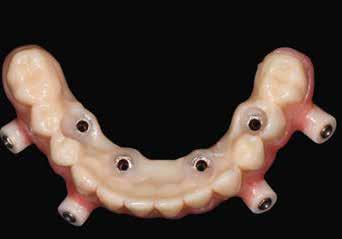

Klinikánkon egy teljesen fogatlan, hagyományos akrilát fogpótlással helyreállított 65 éves férfi beteg jelentkezett, aki nem kielégítő alsó fogsorretencióra és az azzal járó problémákra panaszkodott, beleértve a kifejezetten az alsó fogsorához kapcsolódó gyenge beszéd és rágásfunkciót. A klinikai vizsgálat gömbölyűtől a késhegyig terjedő mandibulagerinc formát és megfelelő vertikális, de nem megfelelő vízszintes csontmennyiséget állapított meg, különösen a hátsó területen (1. ábra) 10

A hagyományos teljes kivehető fogpótlási technikákkal a kezelési stratégia a felső és alsó állcsont kapcsolatának és az okkluzális vertikális dimenzió és a fog helyzetének meghatározását foglalta magában, majd az alsó rögzített restauráció előállításához ezeket használták fel referenciákként (3. ábra) 11